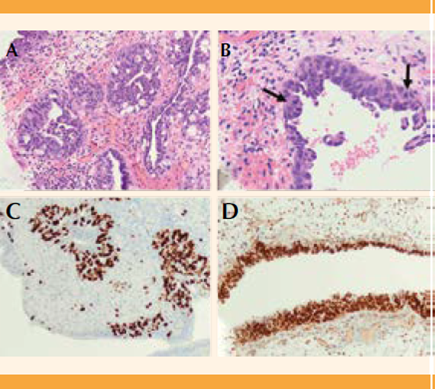

Paciente de 51 años, nulípara, sin antecedentes personales de interés para el padecimiento actual; con una cirugía mamaria por causas estéticas y hemitiroidectomía por hiperplasia nodular. Entre sus características antropométricas se reportaron: estatura de 1.60 m, peso de 55 kg e índice de masa corporal de 21.48 kg/m2. Acudió a revisión ginecológica por elevación de los marcadores tumorales CA-125 (93 U/mL) y CA-19.9 (114 U/mL) y dolor abdominal en la fosa ilíaca derecha de varios meses de evolución. Debido a la dificultad de la exploración ecográfica por vaginismo, se decidió solicitar la resonancia magnética abdominopélvica (pues la abdominal tampoco permitía la delimitación y correcta visualización de los órganos pélvicos), que reportó: útero aumentado de tamaño, comprimido y desplazado por dos masas miomatosas subserosas con escaso componente intramural, una de 60 mm en el lado derecho y la otra de localización un poco más superior de 70 mm (que en su interior tenía una pequeña zona sugerente de degeneración quística). Además, se visualizaban múltiples lesiones de características similares intramurales de menor tamaño. En el anexo derecho se apreciaba una lesión de características quísticas, compatible con endometrioma ovárico derecho de 48 x 30 x 40 mm, aproximadamente, y otra formación de similares características y comportamiento de señal de 12 mm anterolateral, respecto al primero. Se estableció el diagnóstico de útero polimiomatoso y sospecha de endometrioma en el ovario derecho (Figura 1). Se decidió la histerectomía total con salpingooforectomía bilateral por laparotomía, que trascurrió sin complicaciones. Entre los hallazgos intraoperatorios se observaron múltiples adherencias intestinales que bloqueaban el fondo de saco de Douglas, por lo que se decidió conservar el cuello del útero, debido al alto riesgo de lesión intestinal. El reporte definitivo del estudio anatomopatológico de las piezas quirúrgicas demostró la coexistencia de múltiples leiomiomas en el miometrio, algunos con focos de esclerosis, endometrio proliferativo y pólipo endometrial, además del diagnóstico de endometriosis en ambos ovarios y la coexistencia de un tumor de Brenner benigno en el ovario izquierdo. En la pieza de anexectomía bilateral se encontraron, en el estudio microscópico, sobre todo en la región distal fímbrica, focos de carcinoma intraepitelial tubárico seroso, sin identificarse signos histológicos de invasión estromal ni depósitos tumorales en la superficie ovárica ni en la serosa uterina. El análisis inmunohistoquímico reportó positividad en las células tumorales para WT1, apreciándose con Ki67 alto índice de proliferación (Figura 2). Debido a la asociación de este tipo de lesiones con la mutación en la línea germinal BRCA 1 y 2, se solicitó el estudio genético. En la actualidad, los controles mamográficos, la citología cervical y el marcador tumoral CA-125 se encuentran dentro de los parámetros de referencia, la paciente permanece en seguimiento en la Unidad de Ginecología Oncológica, a la espera del reporte de genética.

Figura 2 Carcinoma intraepitelial tubárico seroso. A) Con poco aumento se observa la proliferación del epitelio en pequeños nidos, con arquitectura compleja, pleomorfismo y estratificación nuclear con pérdida de la polaridad (HE,10x). B) A mayor aumento se evidencian las características del epitelio: células con nucleolo evidente, estratificación, pleomorfismo nuclear y pérdida de la polaridad (desorganización nuclear). Además, en un mismo campo, tres figuras de mitosis (flechas). Todo compatible con carcinoma intraepitelial (HE,20x). C) Elevado índice de proliferación celular (Ki67,10x). D) Expresión intensa y generalizada de la proteína supresora de tumores (p53), sugerente del carácter neoplásico de la lesión (p53,10x).